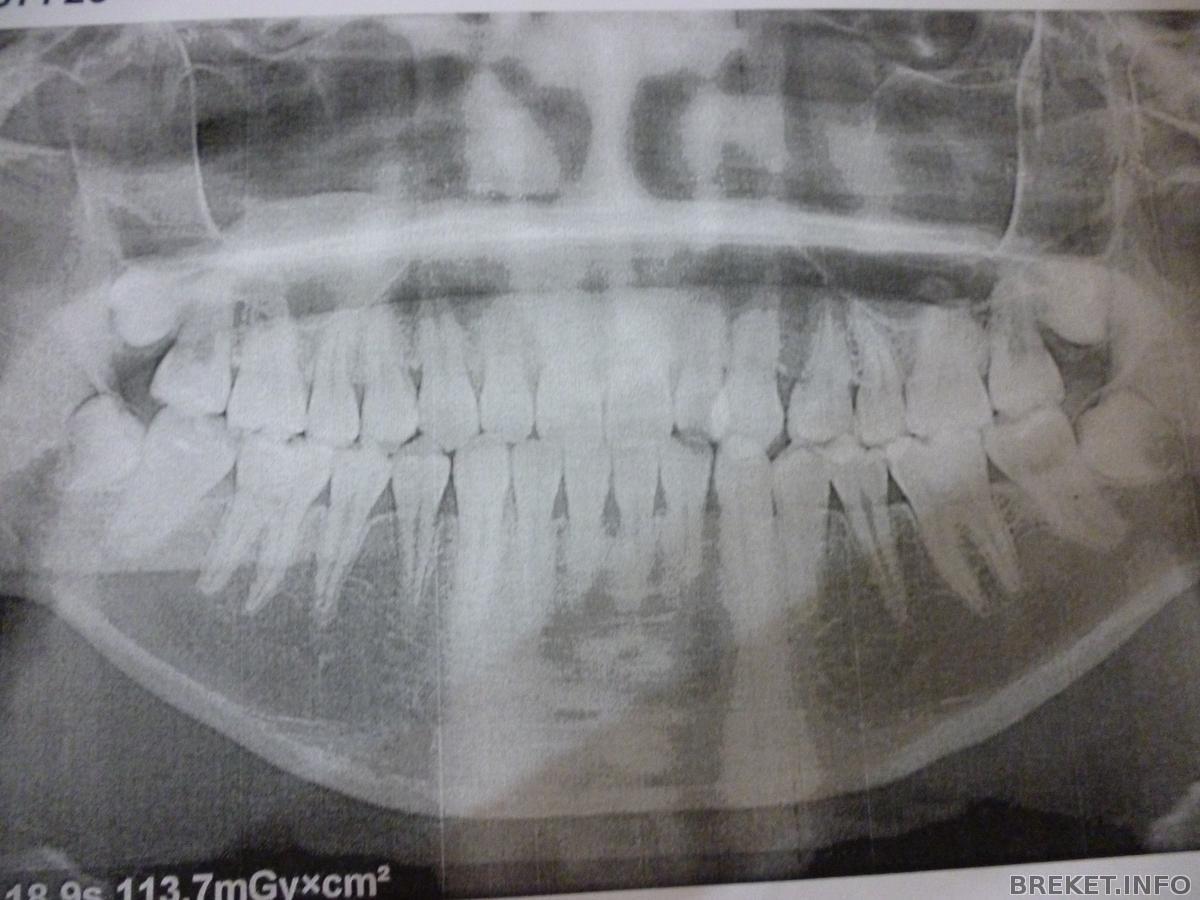

панорамный снимок